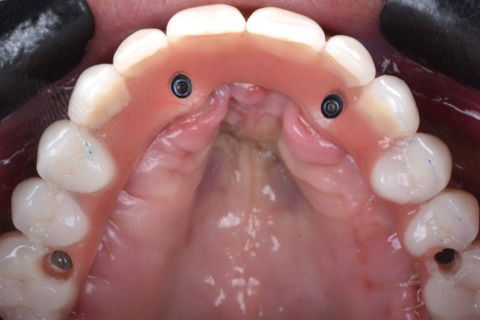

Vista oclusal

Foto 15 Vista oclusal